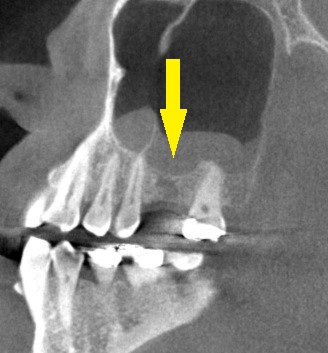

骨の状態を詳しく調べるために、CTを撮影してみると、骨の幅は十分ですが、高さが4~5mmと少なめでした(下の写真、2段目)。

以前なら、ソケットリフトという人工骨を使用した小さな骨造成を併用してインプラントの埋入を行なっていましたが、現在はワイド径のインプラントを使用することで、人工骨を使用しないで埋入を行ないます。